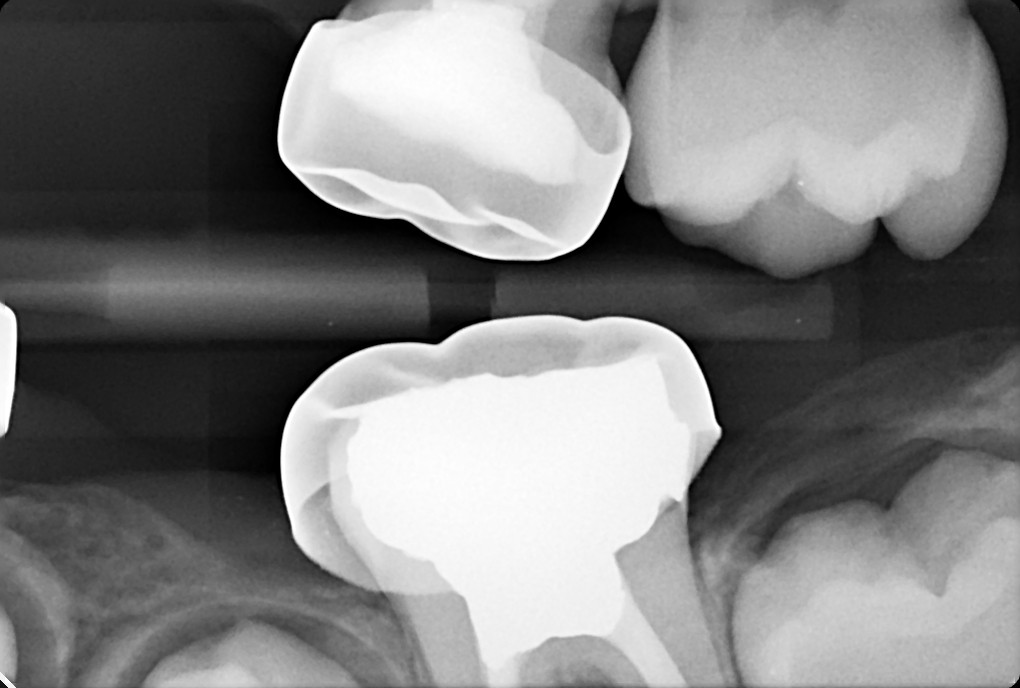

1. What option can explain the crown of the tooth # 1.4?